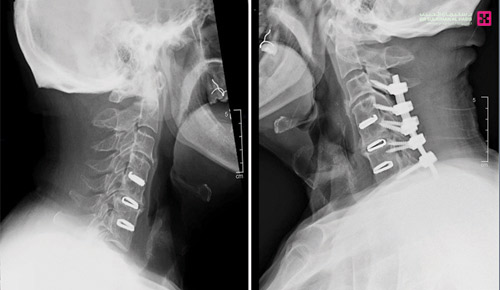

وقد خلص الفريق الطبي إلى خطة علاجية، وأُجريت له عمليتان بوقت واحد تم فيهما تحرير العمود الفقري من الضغط بإزالة الانزلاق الغضروفي وتثبيت الفقرة الرقبية رقم «3» وتوصيلها للفقرة العنقية السابعة، تحت جهاز المراقبة العصبية، واستمرت العملية لنحو «3» ساعات، وبعد ذلك تم إجراء عمليتين باليد اليمنى واليسرى لتحرير النفق الرسغي ومضت بسلاسة وانتهت ولله الحمد بالنجاح التام.

وبعد العمليات أمضى المريض «5» أيام في قسم التنويم تحسنت حالته خلالها واستعاد قدرته على المشي بعد نحو «36» ساعة من العملية، وغادر المستشفى وهو بحالة صحية ممتازة، وقد تخلص من الأعراض التي كان يشكو منها وتحرر من قيود ضعف الحركة وعاد لممارسة حياته بصورة طبيعية بدون ألم.